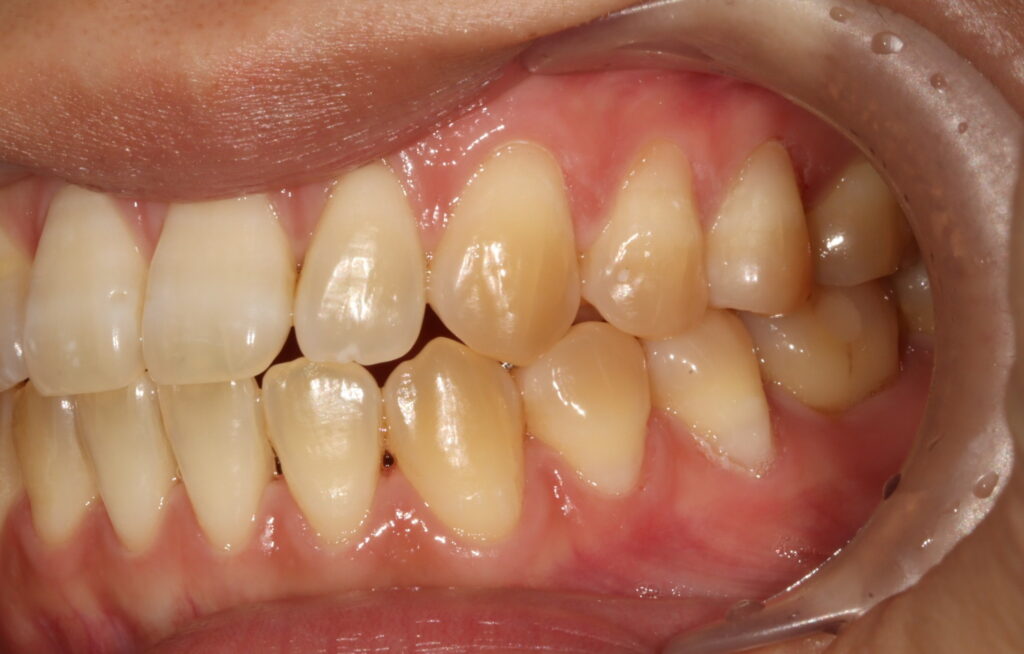

치료 종결 25.07.18

치아색에 맞는 레진으로 치경부 마모를 충전한 모습입니다. 내원하신 날 바로 진행하여 빠르게 불편함과 심미성을 회복하셔서 환자분께서 매우 만족해하셨어요:)

영도치과 서울 화이트S치과는 치료에만 중심을 두지 않고, 앞으로 이러한 마모 진행이 되지 않도록 환자분의 잇솔질 방법과 평소 생활습관을 직접 상담을 통해 확인하고 올바른 구강관리방법을 안내해드리며 정기적인검진으로 늦지않게 치료받으실 수 있도록 도와드렸습니다.